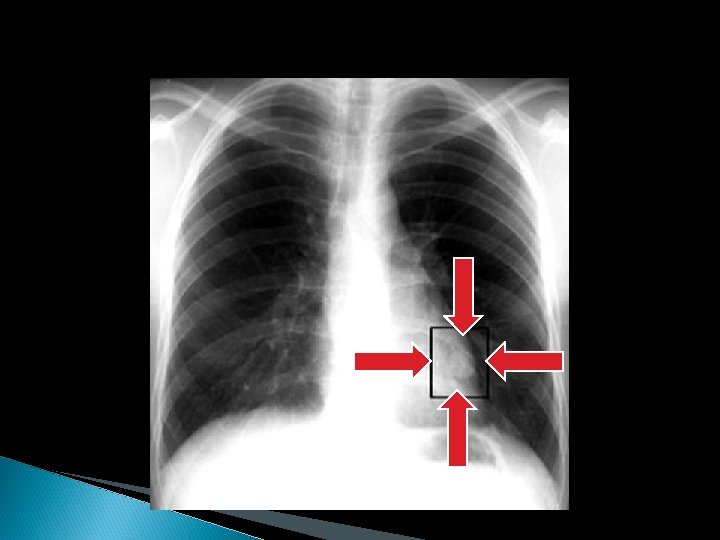

METODOS DE IMAGEN RX DE TORAX: Sigue siendo el procedimiento básico mas importante y tiene una eficacia global del 7088% para diagnostico de sospecha de la enfermedad. En un 5 -15% de los casos antes de aparecer los síntomas el único dato que permite sospechar la existencia de un CP es la presencia de alguna anormalidad en la misma.

Manifestaciones radiológicas: 1: - Anormalidades en región hiliar con aumento o prominencia de la densidad hiliar. 2: - Alteraciones del parenquima pulmonar: Nodulo (menor o igual de 4 cms), Masa (mayor de 4 cms), Masas multiples, Evidencia de obstrucción bronquial (colapso). . . 3: - Alteraciones de las estructuras intratorácicas extrapulmonares: ensanchamiento o masa mediastinica, erosion o destruccion de costillas o vertebras, derrame pleural y elevacion diafragmatica.